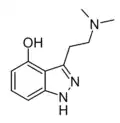

I-32 [33] | 3-(1-methylpyrrolidin-3-yl)-1H-indol-4-ol | |

|

2-Azapsilocin (Psilocin indazole analogue, P-6)[34] | 3-[2-(dimethylamino)ethyl]-1H-indazol-4-ol | |

|